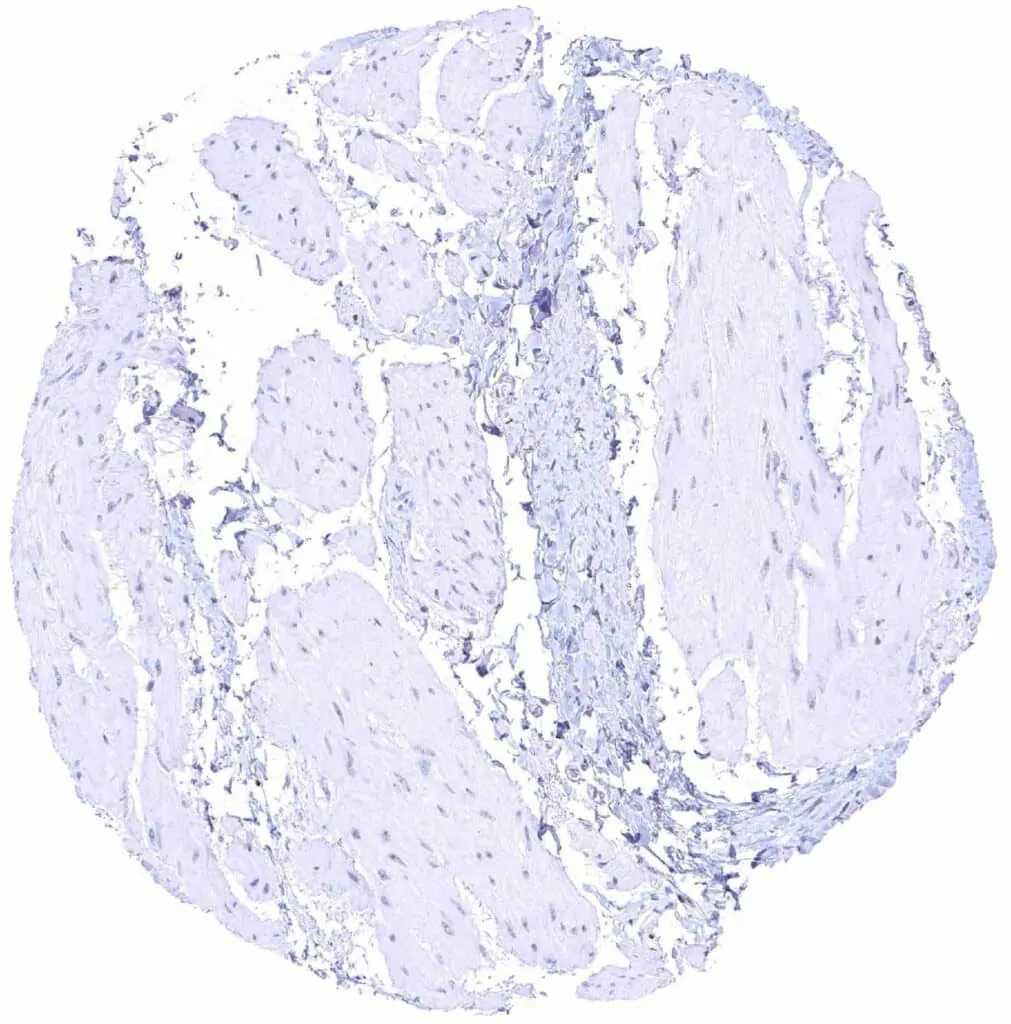

Heart muscle